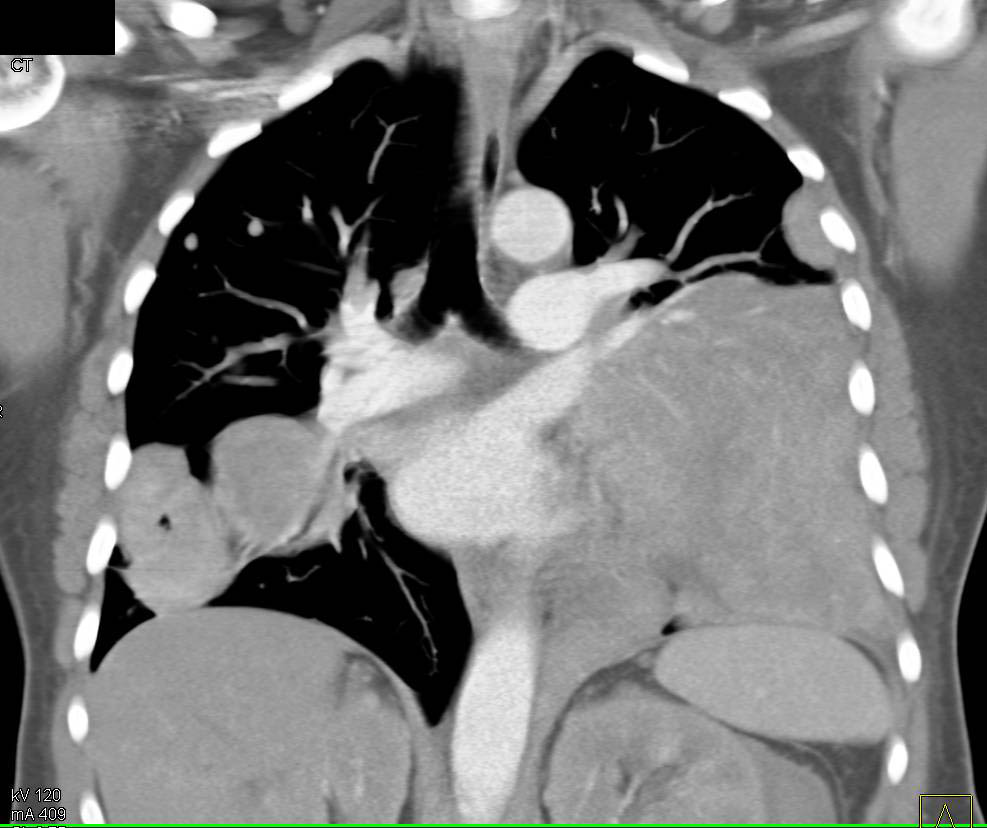

Lymphoma with Mediastinal, Lung Parenchymal and Renal Involvement What Is Lung Parenchymal Involvement Parenchymal lung diseases are disorders that affect the pulmonary interstitium. The lung parenchyma is the vital portion of the lung that participates in gas exchange. Lung parenchyma is the portion of the lung involved in gas transfer, predominantly the alveoli. What happens when you have interstitial lung disease?. The lung parenchyma denotes alveolar tissue with respiratory bronchioles, alveolar ducts, and. What Is Lung Parenchymal Involvement.